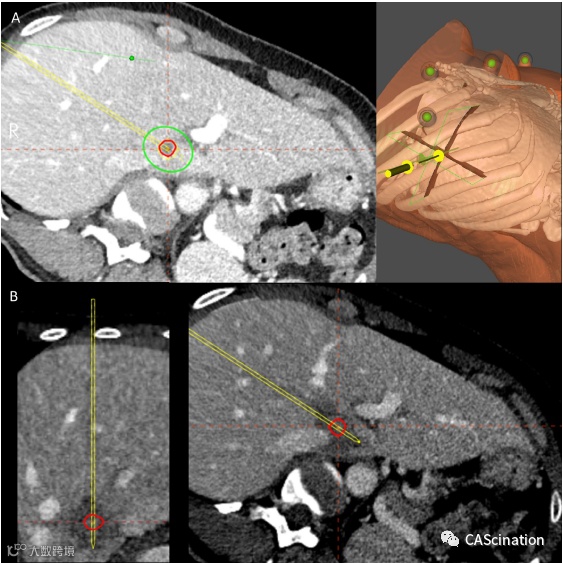

规划阶段的初始CT扫描显示肝I段有直径为8 mm的已知转移(图2A)。消融探针(Accu2ioTMA, Angio-dynamics, NY)经皮穿刺肝组织11 cm。进行第二次扫描,可查看消融针的位置是否精确。导航装置内的规划软件可确定具有足够安全边界的消融区域,同时可避免伤害到重要的血管结构(图2A)。

软件计算出所需能量的强度和持续时间,按计划进行微波消融,功率100W,持续2分钟。术后再进行一次CT扫描,通过术前术后的CT扫描对比,(图2B)显示消融面积为30×16 mm,完全符合计划且覆盖初始病灶,也提供了足够的安全边界。下腔静脉和左门静脉未受影响。

图2-之前的mwa三维消融区域规划(a)支持在避开敏感血管结构的同时精确定义安全边界。

介入治疗后对照(B)显示计划组织和治疗组织之间几乎完全匹配。